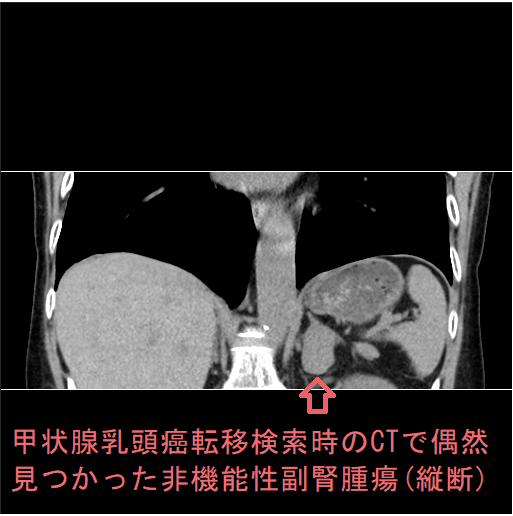

全身拡散強調MRI検査(DWIBS:ドゥイブス )で副腎偶発腫瘍(インシデンタローマ)を見つける場合があります。

写真は、甲状腺濾胞癌手術後の遠隔転移検索で行った全身拡散強調MRI検査(DWIBS:ドゥイブス )の際、偶然見つかった副腎腺腫(原発性アルドステロン症)。